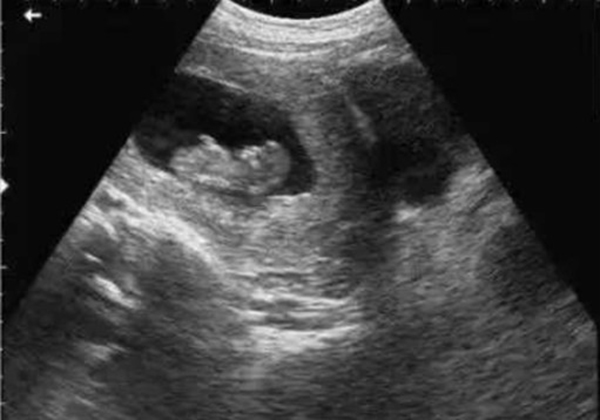

• 超声检查(B超/彩超):它利用超声波的反射原理成像,就像“用声音给身体拍照片”,没有任何辐射。无论是孕期产检(观察胎儿发育)、腹部检查(排查肝脾胆囊问题),还是甲状腺、乳腺等浅表器官检查,超声都是首选。而且超声检查灵活便捷,还能实时动态观察器官运动(比如心脏跳动、胎儿胎动),是临床中应用最广泛的“安全检查”。

当然,在非紧急情况下,医生会优先选择超声或MRI。比如孕妇产检,超声是核心检查;婴幼儿排查脑部问题,MRI是更安全的选择。关键在于“权衡利弊”,而非“一刀切”拒绝。